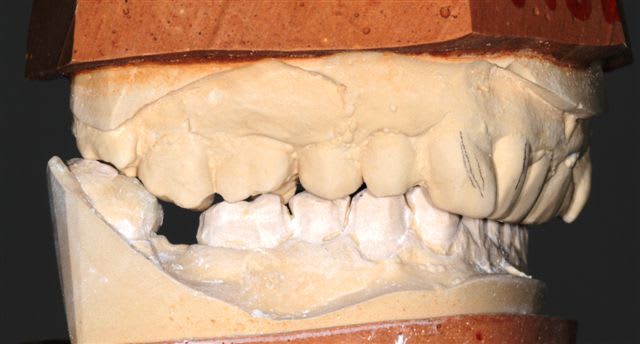

Il semble évident que ceci ne peut être traité que de façon globale, mais la difficulté est de le faire comprendre à la patiente, qui veut seulement un "sourire".

Donc dans un premier temps pano, pour bilan et empreintes pour essayer de lui faire comprendre l'étendue du problème.

premier wax up à minima

Mais autant un wax up ça nous parles, autant la patiente ne déclenche pas, et commence à douter.